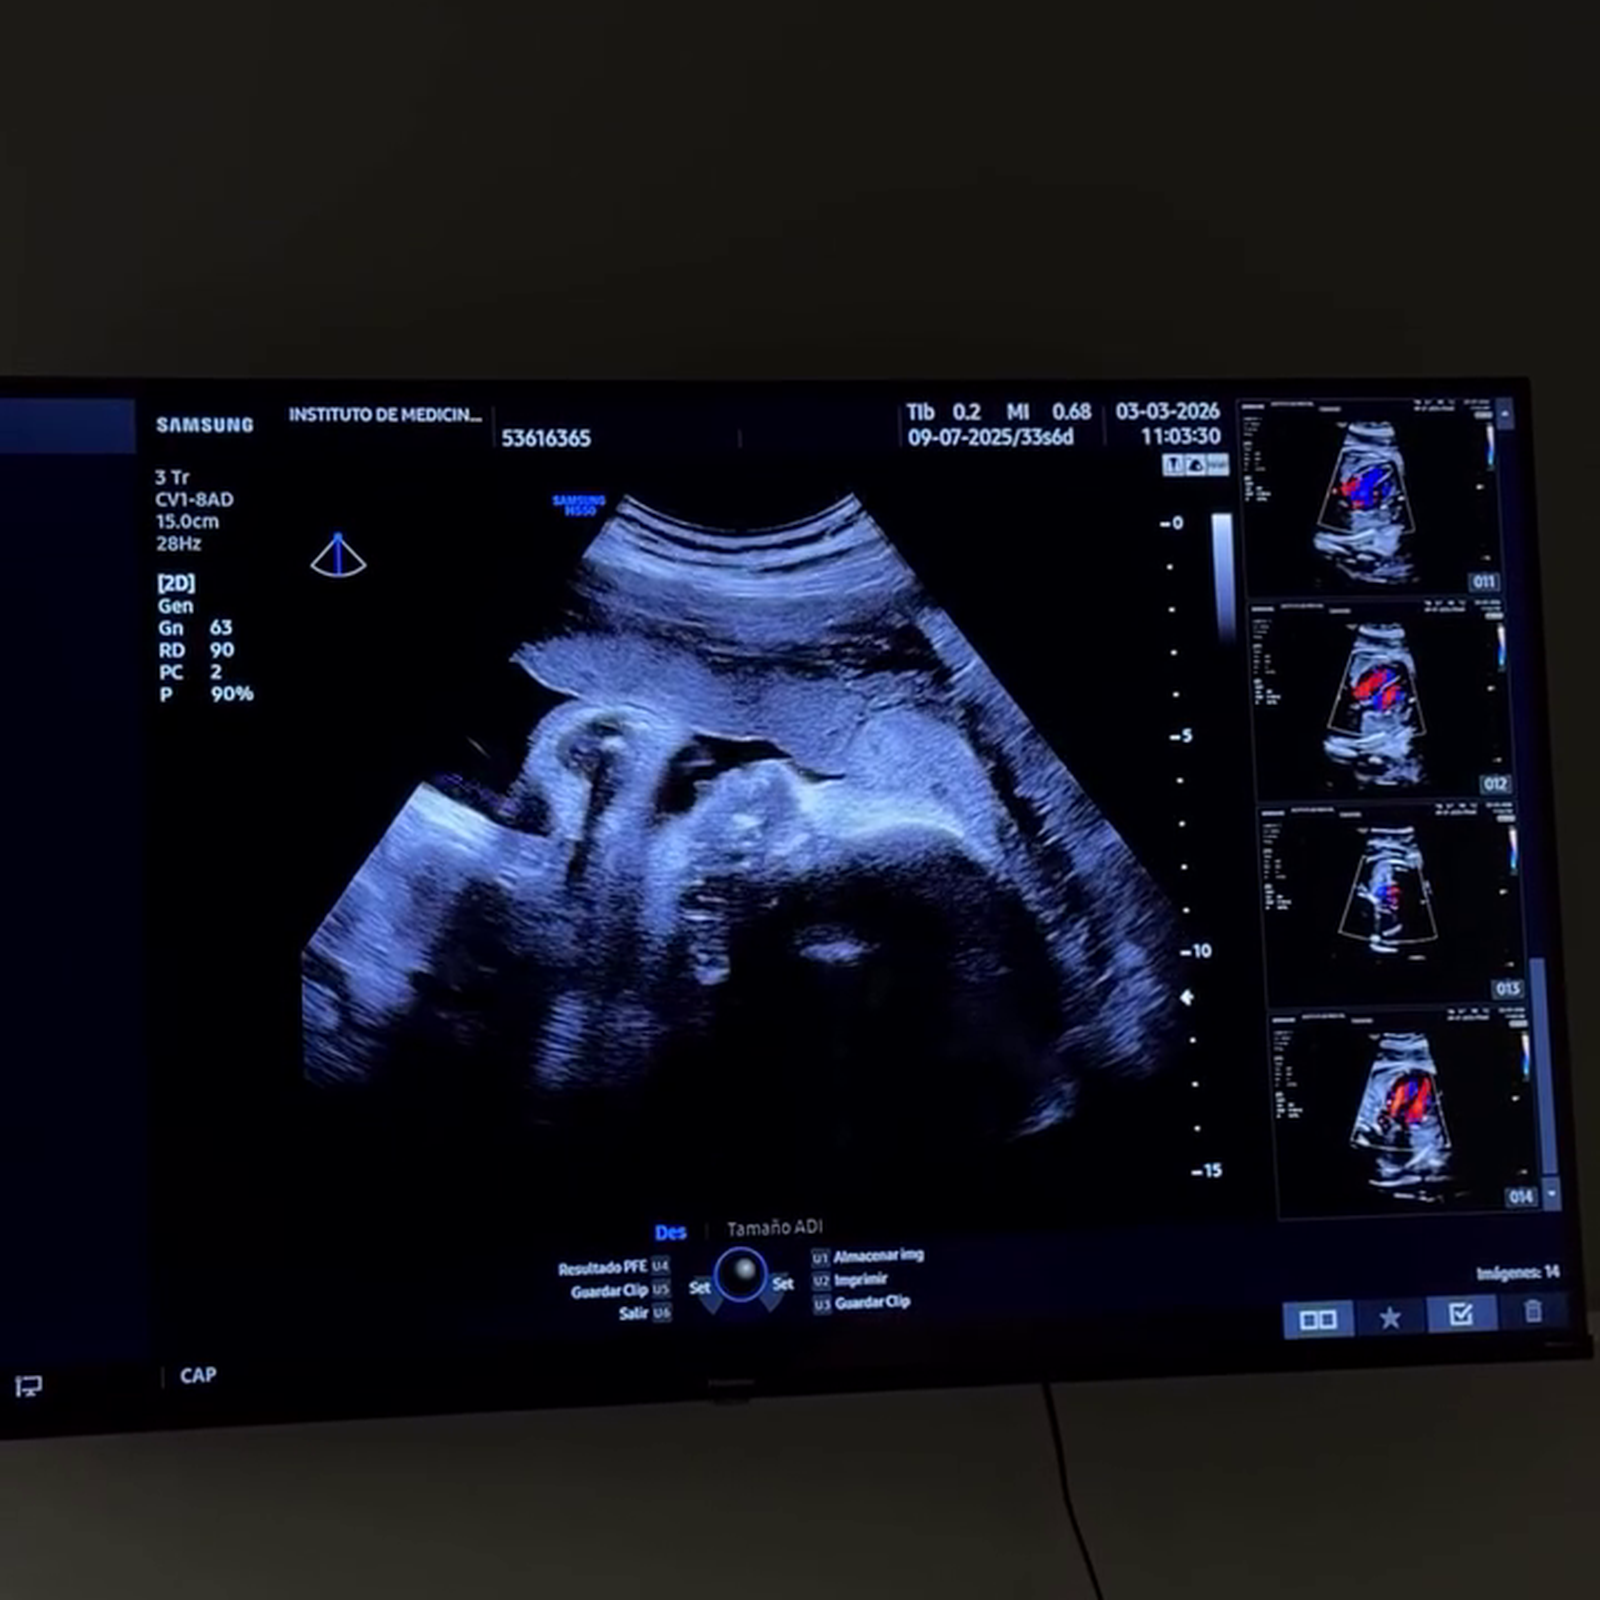

Marta Castro y Rodri Fuertes están a punto de convertirse en padres. A la exconcursante de ‘GH VIP’ le quedan apenas siete semanas para llegar a su fecha probable de parto y los nervios son evidentes. La pareja ha acudido a una impartente cita médica con su ginécologo y han compartido con sus seguidores cómo está su hija y cuánto pesa. Además, el influencer habla de algo tan importante como es la depresión postparto.

Tras hablar abiertamente sobre los kilos que ha cogido ella durante el embarazo, la influencer desvela ahora el peso de su pequeña. “Infórmanos sobre cómo está la gorda”, le dice a Rodri mientras se graban al salir del médico. Estas últimas semanas son cruciales pues durante el octavo mes, que es en el que está Marta, los bebés ganan aproximadamente la mitad de su peso total al nacer, acumulando grasa, madurando órganos y aumentando drásticamente de volumen.

Su hija está dentro del percentil y los influencer no pueden estar más tranquilos y felices. “2,200kg, percentil estupendo”, ha anunciado Rodri con una sonrisa en la boca. Marta ha intentado cuidarse lo máximo posible durante estos meses y el esfuerzo ha tenido resultados. “Está sanota como la madre”, ha dicho Rodri aliviado.